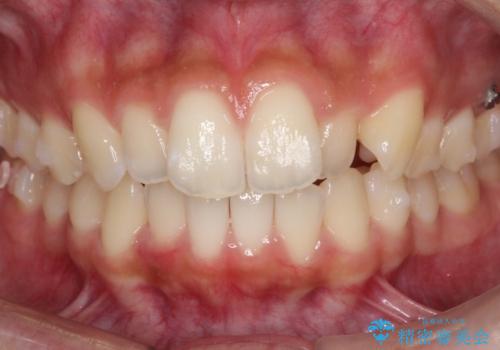

- 前歯の歯並びの改善を希望され来院された患者様です。

初診時の歯並びの状態としては、上下ともに全体に及ぶの中等度のがたつき(叢生)があり、全特に左上の前歯は1本だけ引っ込んでいる状態でした。